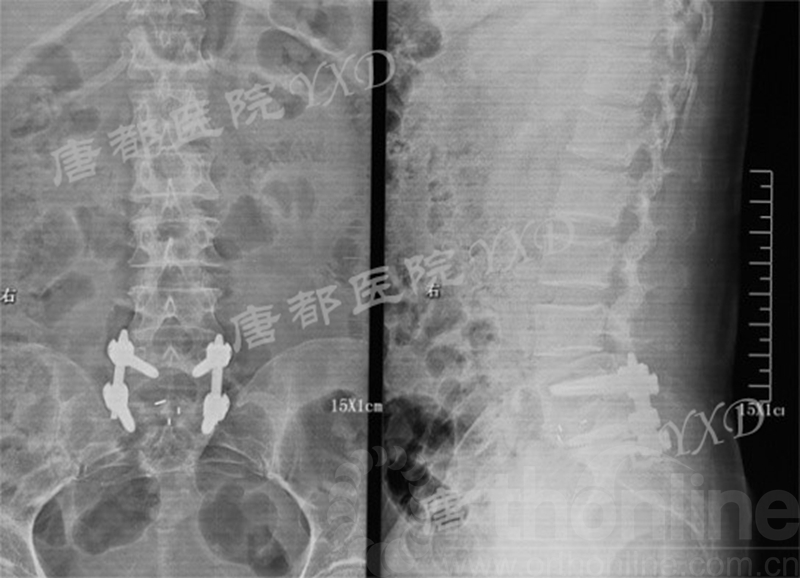

影像学检查:

诊断:腰椎间盘突出症术后复发

手术方案:显微镜辅助MI-TLIF腰椎翻修术

术后疗效:VAS评分右下肢1~2;腰2;右侧直腿抬高试验、加强试验阴性;行走自如、步态无异常。